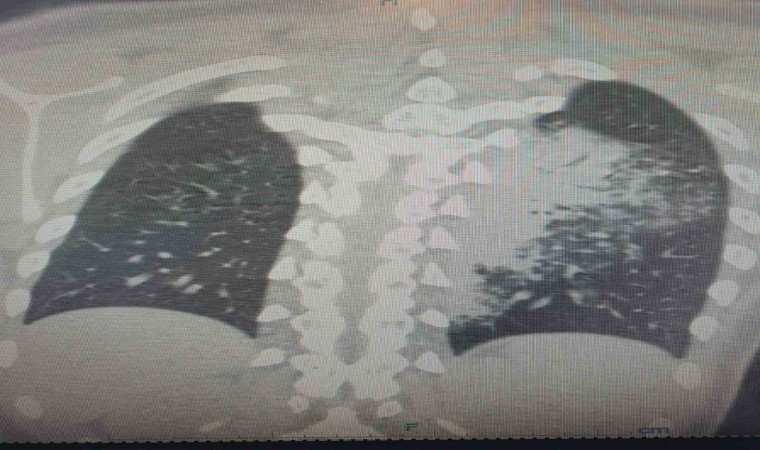

Göğüs Hastalıkları Uzmanı Prof. Dr. Şevket Özkaya, özellikle otel ve tatil köylerinde konaklayan kişiler arasında “beni klima çarptı” diyen neredeyse her iki kişiden birinde bu hastalıkların saptandığını belirtti. Prof. Dr. Özkaya, bu durumdan en çok etkilenenlerin ise çocuk yaş grubu olduğunu vurgulayarak, “Ciddi sayıda, daha önce görülmemiş derecede çocuk bronşiti ve zatürresi vakaları görmeye başladık. Hatta COVID-19 salgınında, çocuk yaş grubunda COVID-19 virüsüne bağlı bu kadar çok zatürre görmüyorduk. Son günlerde; ‘Legionella’ bakterisinin, çocuk yaş grubunda COVID-19’a oranla çok daha fazla zatürreye neden olduğunu görüyoruz” diye konuştu.

Legionella pneumophila isimli bakterinin klimalardan üremesi sonucunda hastalığın ortaya çıktığını belirten Prof. Dr. Özkaya, bu hastalığın kronik rahatsızlığı olanlarda ölümcül olabileceğini ve yaşlı, kronik hastalığı olan vatandaşların dikkatli olmaları gerektiğini hatırlattı.

Özellikle klimaların iyi temizlenmesi gerektiğini belirten Prof. Dr. Özkaya, klima zatürresinde şikayetlerin daha az olduğu için grip gibi eklem ağrıları, ateş, halsizlik, ishal gibi hafif soğuk algınlığı belirtileriyle seyrettiği için çok fazla anlaşılmayabileceğini söyledi. Kronik hastalığı olanlarda hayati sonuçlar da doğurabileceğini belirten Özkaya, “Pandeminin bitmesiyle beraber ani ısı değişikliklerine, soğuktan sıcağa geçişlere ve klimalara maruz kalmak, grip ile karıştırılabilir ve önemsenmeyebilir. Çocuklar ise ne hissettiklerini anlatamadıkları için uzamış öksürük ve ateş şikayeti ile doktora başvurduklarında ciddi zatürre vakaları ile karşı karşıya kalırlar” dedi.